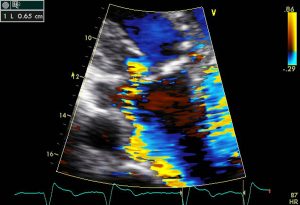

其次,心脏瓣膜病的评估和管理正在变得越来越复杂,然而许多心脏瓣膜病的患者仍被一般的医生或心脏病学家都在没有专业专业知识。对于可能缺乏诊断的医生或心脏病学家对这种疾病的评估可能难以做出诊断的诊断,特别是在确定患者是否真正无症状。该决定用于共存二尖瓣反流(一种无能或漏水的二尖瓣,使得通过心脏的血液向后流动)或者在冠状动脉旁路接枝时更换具有温和或中等狭窄的主动脉瓣的可取性也是如此经常难。瓣膜病评估涉及多种方式的整合,并且实践的进步可能比具有专业专业知识的心脏病专业的通用主义者更慢入。心脏瓣膜疾病的患者通常具有可造成症状的合并症,从而将决策复杂化,如果指出干预。确定正确的程序,无论是修复,替代或经沟管手术,都不简单,还需要专业知识,经验和多学科讨论。